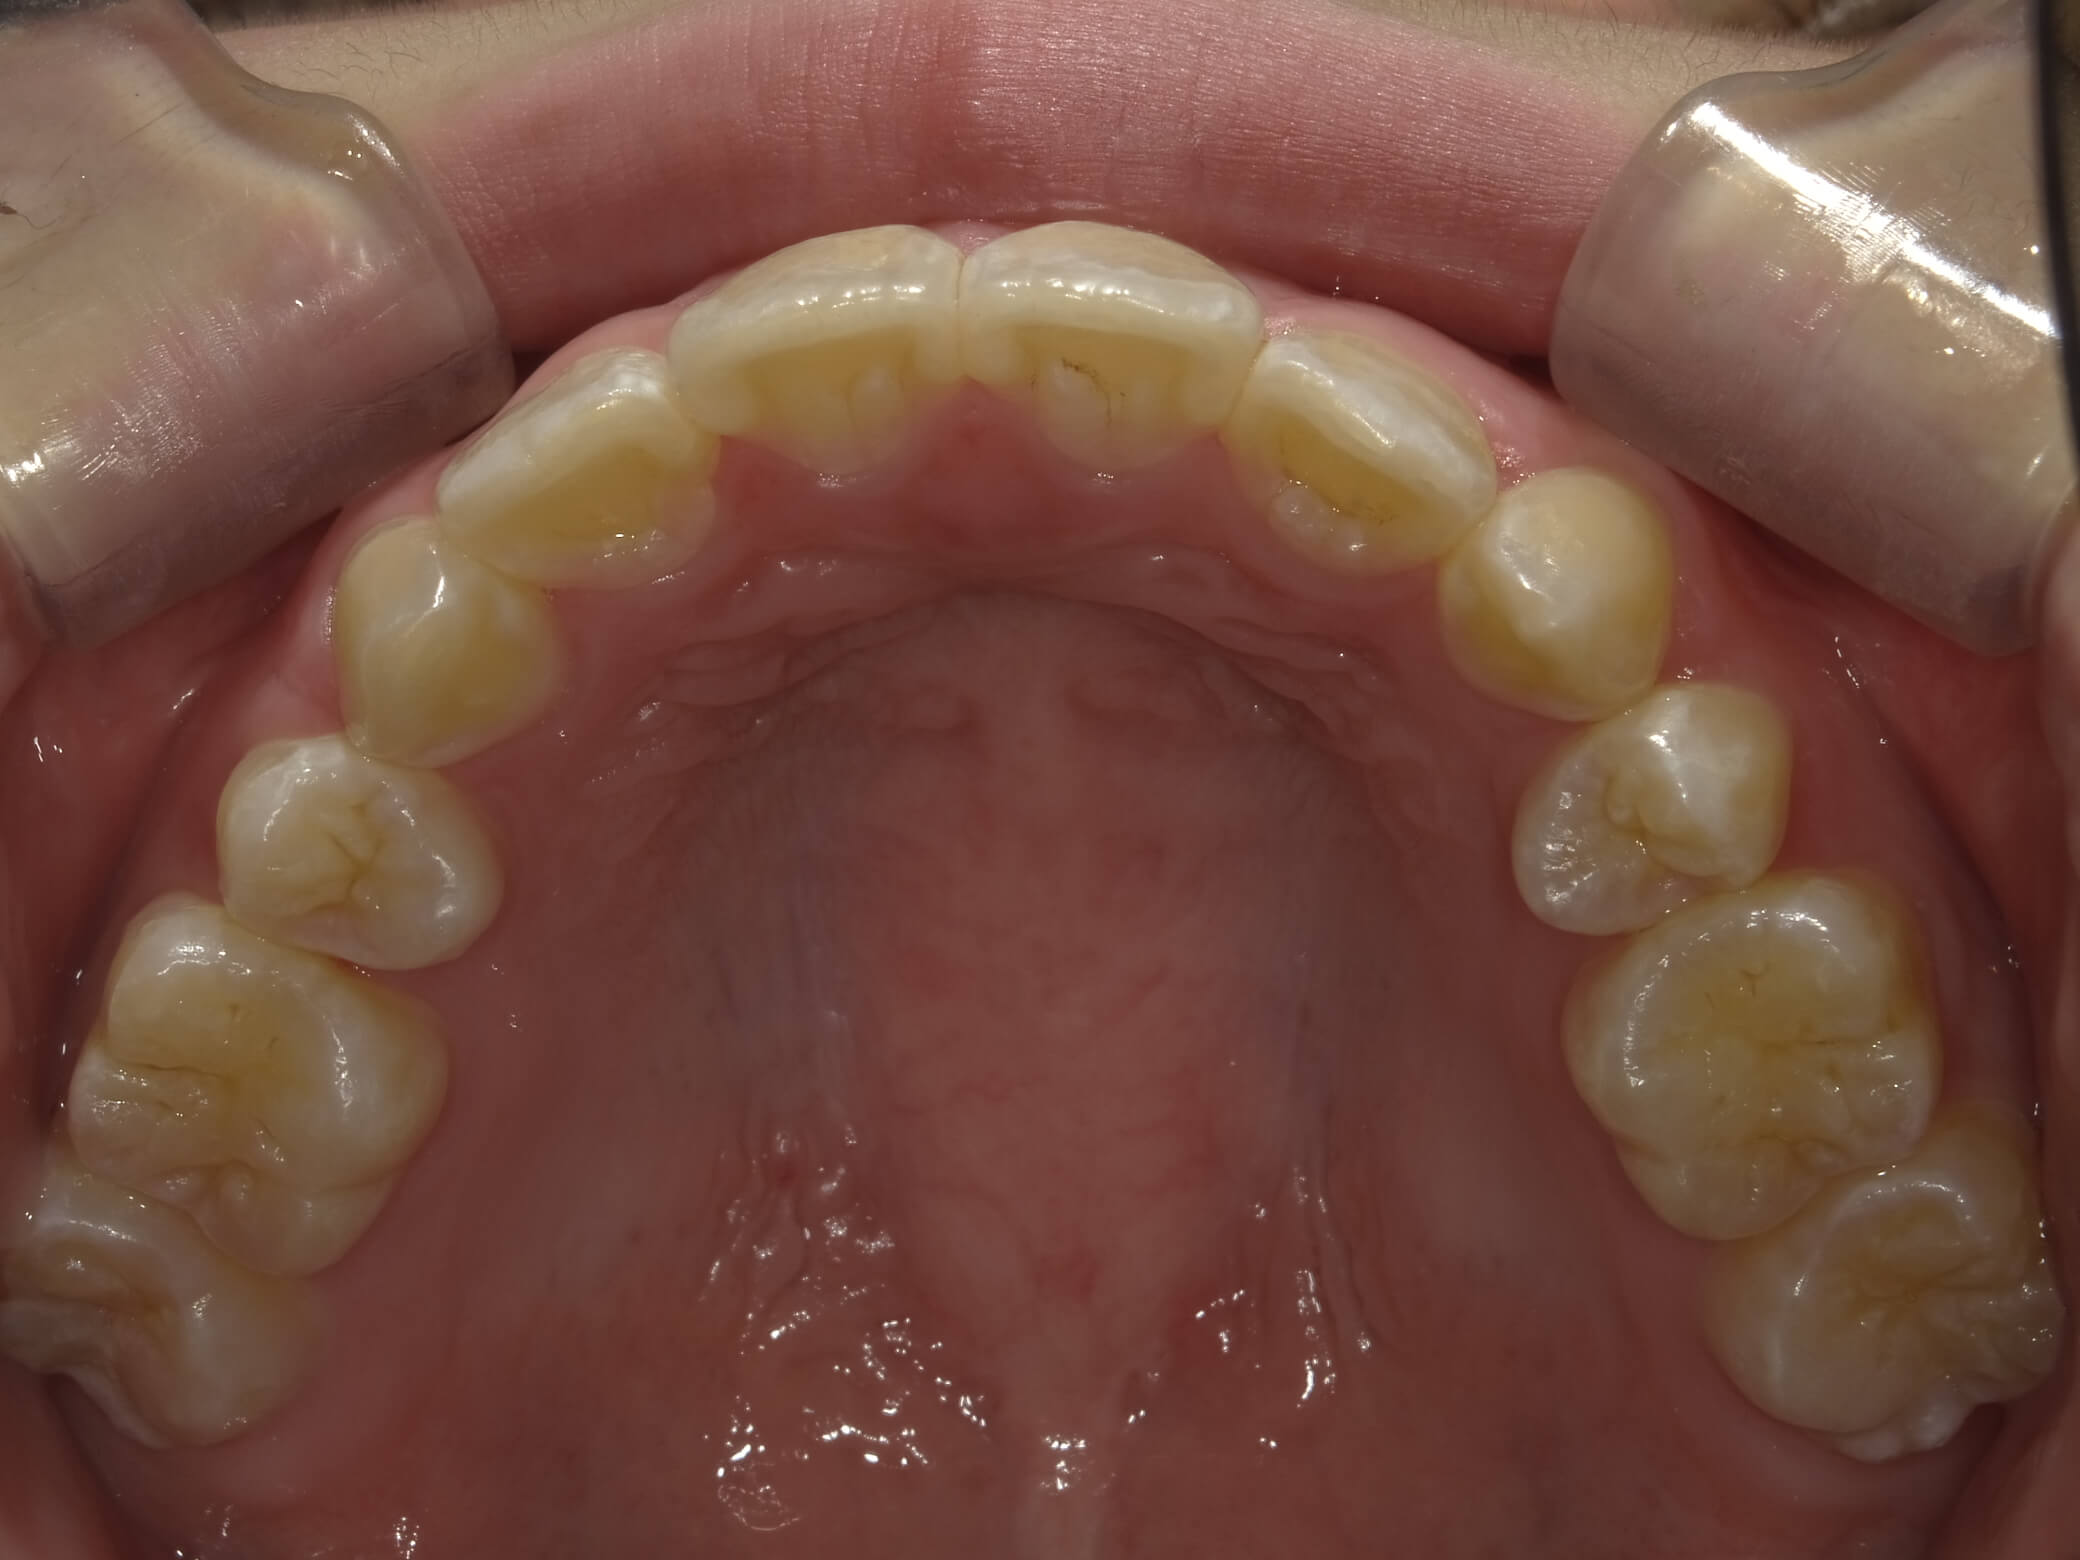

• 治療前

• 治療後